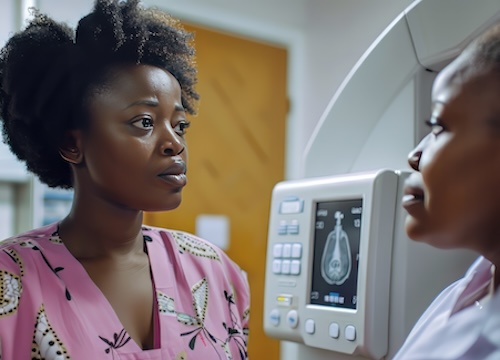

Women with limited English-language proficiency (LEP) get mammogram screenings for breast cancer less than other women, according to a study presented at the American College of Surgeons (ACS) Clinical Congress 2020.

In this study, researchers assessed a total of 9,653 women, of which 1,040 had LEP, and 756 spoke only Spanish. The study subjects were all between the ages of 40 and 75 – the age range usually recommended for mammography screening.

The results showed that of 936 LEP group members who provided mammogram information, the overall rate of screening mammograms was 12% less than for proficient English speakers. Of 209 women with LEP who reported never have undergone a mammogram screening, the researchers observed via statistical analysis of the entire US female population in the 40-75 age range that it equaled approximately 450,000 women in the country who are eligible for mammogram and may not have had one.

“Spanish-only speakers appear to have a 27 percent less likelihood of having a screening mammogram than English speakers,” said lead study investigator Jose L. Cataneo, MD, a general surgery resident at the University of Illinois at Chicago (UIC)/Metropolitan Group Hospitals via a press release.

“The impact of language barriers on screening mammography was previously unknown from a national database,” Dr. Cataneo added. “It is important because approximately 67 million people in the United States speak a language other than English, and 41 million of those speak Spanish.” He cited recent U.S. Census Bureau estimates.

Many reasons probably exist why low English proficiency is linked to reduced mammography screening rates, according to senior investigator, Celeste Cruz, MD, a breast surgeon at Advocate Illinois Masonic Medical Center in Chicago. For instance, women with LEP were more likely than others to be poor and lack health insurance. To address the language-based disparity in mammography screening rates, she said her hospital is increasing educational efforts about breast health, the importance of screening, and advances in breast cancer treatment.